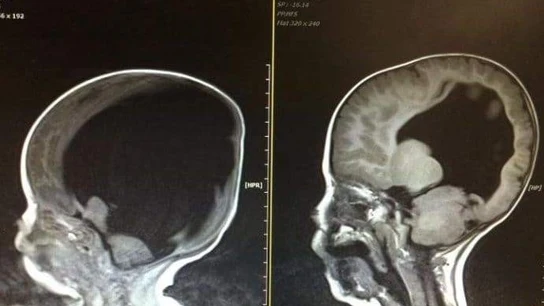

Noah nació sólo con el 2% de la función cerebral y los médicos pronosticaban que no sobreviviría, y si lo hacía, sería con discapacidades severas. Con cuatro años, Noah sabe contar hasta diez, cantar e incluso jugar a videojuegos.

En 2012 en Abbeytown llegó al mundo Noah, un niño que nació sólo con el 2% de su capacidad cerebral, espina bífida e hidrocefalia, y al que los médicos daban pocos días de vida.

El pequeño no solo consiguió sobrevivir, sino que además su cerebro ha seguido desarrollándose hasta llegar a tener uno similar a un niño de su edad, algo que los expertos catalogan como "milagro médico".